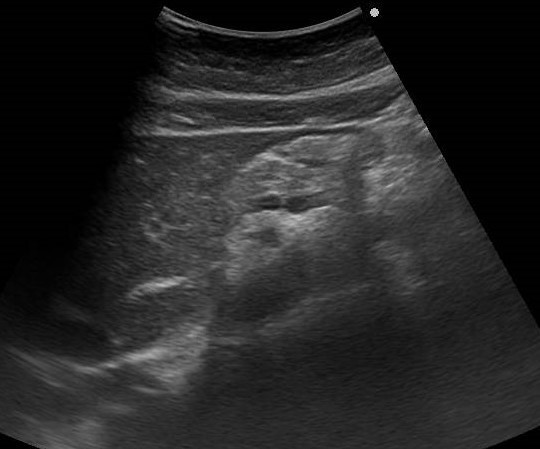

腹部超音波(エコー)検査は体表からプローベを当てて、超音波を深部に伝え、その反射具合により臓器や病変を確認する検査です。

病変サイズもすぐに確認できます

またポリープや腫瘍、結石などの大きさの変化などもすみやかに確認できます。

大きな胆石が見つかることも!

患者さんの中には、「少し前から胃が痛くて・・・」という症状で来院される方がいます。胃のあたりをさすって症状を伺いますが、おなかには胃だけではなく多くの臓器が複雑に存在し機能しています。胃潰瘍やポリープの診断は内視鏡が得意な分野ですが、消化管の外を見ることができる超音波と組み合わせることで、格段に症状に関連した情報が増えます。